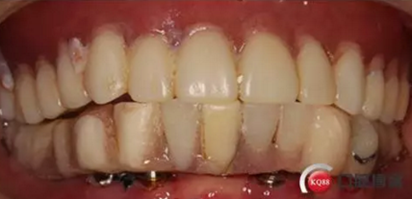

戴牙:試戴,拍片確定邊緣密合后調(diào)整咬合,試戴一周后患者適應(yīng),咬合良好,基臺(tái)加力30N.CM,粘接劑粘固,去除多余粘結(jié)劑,拍片確定有無(wú)粘接劑殘留,并進(jìn)一步微調(diào)咬合

微笑是最美的溝通語(yǔ)言,患者的滿意是我們的追求

6)6個(gè)月后復(fù)查,修復(fù)體密合性均良好,修復(fù)效果符合預(yù)期,醫(yī)囑患者做好口腔衛(wèi)生預(yù)防種植體周圍炎

結(jié)果:本病例在觀察期內(nèi),種植修復(fù)獲得了良好的美觀功能的穩(wěn)定性